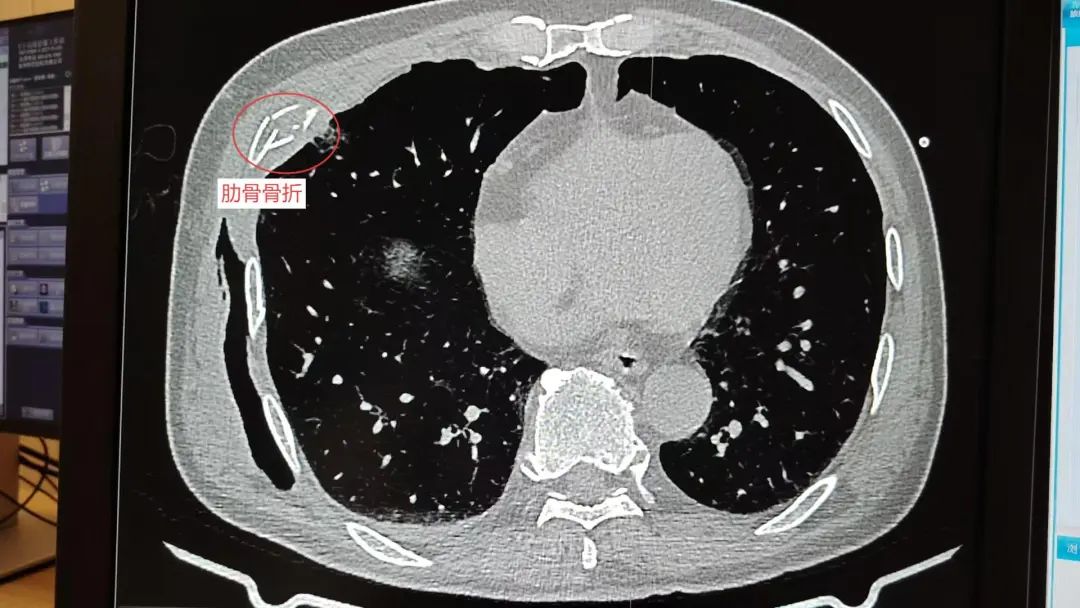

多处骨折

皮下气肿

系统检查提示:罗叔目前存在车祸后多发伤,头部、胸部、腹部等存在多处外伤,颅脑的挫裂伤,右侧颌面部撕裂伤,右肘关节皮肤裂伤等全身多处皮肤擦伤。外表的伤口已经足够狰狞,而在罗叔的身体内部存在更严重的情况:闭合性颅脑损伤、呼吸衰竭、右侧6根肋骨骨折伴血气胸和皮下气肿、代谢性酸中毒、呼吸性碱中毒,还有肝、肺挫伤等脏器损伤。